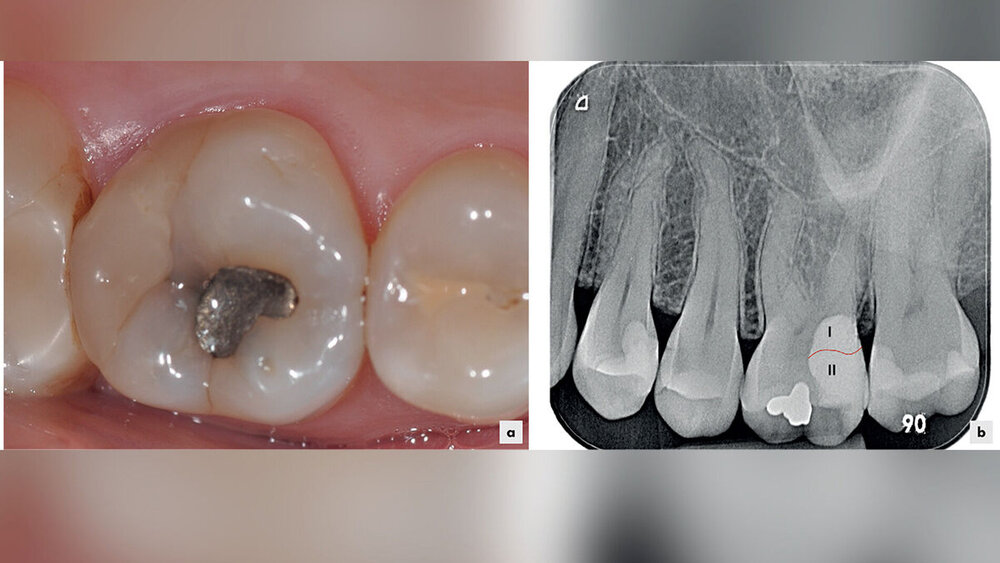

Mit einer speziellen Technik ist es möglich, dieser Anforderung nachzukommen, wenn man Kompositrestaurationen anfertigt, die tief subgingival enden. Dabei wird zunächst der gingivale Restaurationsrand mithilfe der „Schneepflugtechnik“ (snowplough-technique) angehoben und anschließend in einem zweiten Schritt die Kompositrestauration vervollständigt. Bisher gibt es zu dieser Technik hauptsächlich Fallberichte beziehungsweise In-vitro-Studien, die allerdings eine begrenzte Aussagekraft bezüglich der allgemeinen klinischen Anwendbarkeit besitzen. Die bisher veröffentlichten klinischen Studien beziehen sich häufig auf die Stufenelevation mit anschließender indirekter Restaurationstechnik. Die vorliegende Studie beschäftigte sich nun mit rein direkten Restaurationen in der oben beschriebenen Technik und untersuchte, ob es zu gingivalen, parodontalen Entzündungszeichen kommt, wenn die Technik verwendet wird.

Bei der Restauration wurde die oben beschriebene Zwei-Schritt-Technik verwendet. Nach der Kariesentfernung wurde der approximale Kavitätenrand angehoben, Kofferdam wurde nicht gelegt, die Feuchtigkeitskontrolle erfolgte mit Watterollen und Absaugung. Zudem wurden Retraktionsfäden gelegt. Es wurde ein Drei-Schritt-Etch-and-Rinse-Adhäsivsystem verwendet und ein Flowable mit einem Hybridkomposit eingebracht. Dabei kam die „Schneepflugtechnik“ zum Einsatz und mögliche Überhänge wurden sorgfältig entfernt. Anschließend wurde Kofferdam gelegt und unter Anwendung einer Teilmatrize und eines Keils der okklusale Teil einer Kavität eingebracht. Dann wurde die Restauration finiert und poliert.

Offensichtlich werden glatte, randspaltfreie Kompositrestaurationsränder vom parodontalen Gewebe gut toleriert. Es sollte zusätzlich erwähnt werden, dass die Anfertigung der tief subgingival endenden Restaurationen sehr techniksensitiv ist und daher sehr sorgfältig durchgeführt werden sollte. Speziell die Kontrolle des gingivalen Randes der Restauration ist häufig nur mit einem Röntgenbild möglich.